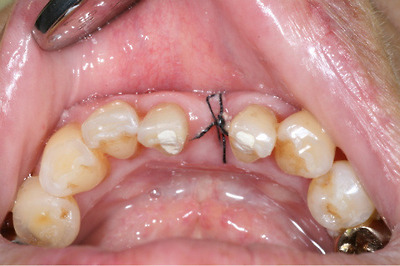

환자분 41부위 발치 후 치은이 V자 홈이 파진채로 회복되어 FGG를 통해

volume을 회복하고자 했던 증례입니다... 수술직후 사진이 집에 있어서

일단 술후 1주 사진만 먼저 올려요...

suture는 site가 고랑같이 깊어서 가로로는 suture하기 힘들더군요. 어쨌든 눌러는 줘야 할거

같아서 그림그려놓은거처럼 해서 눌렀어요...